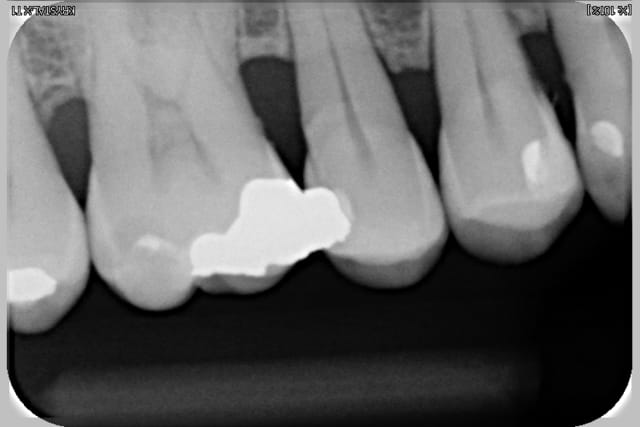

Radio 36 2009 liviaq - Eugenol

Radio 16 2009 alhcqr - Eugenol

Radio 25 2009 pd2mbc - Eugenol

Radio 46 2009 eomewu - Eugenol

Voir images

On peut y voir une remodelage osseux, de tartre, l'usure de la canine